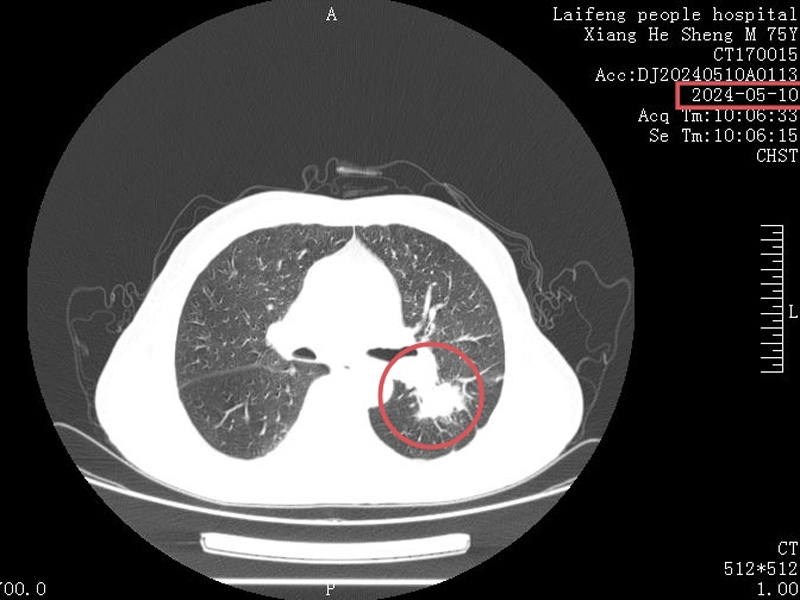

黎小兵博士在详细了解患者病情后,带领肿瘤科医护团队为向先生制订了个性化治疗方案,在经过4个周期的精心治疗后,向老先生肺部的肿瘤明显缩小,病情也得到了明显改善,对生活又充满了希望,全家人也都为此感到开心。为了表示感谢,特地向我院肿瘤科赠送锦旗。

治疗后